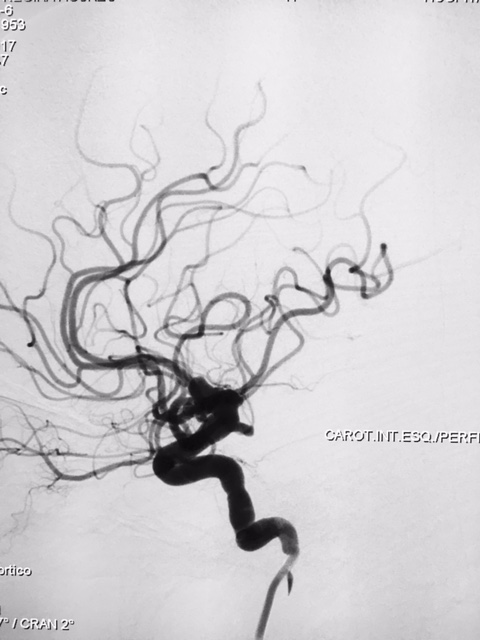

Aneurisma de topo da carótida

SNA. 76 anos. Durante investigação ambulatorial de cefaléia e tremor nas mãos foi realizado Angiotomografia de crânio evidenciando aneurisma incidental em topo da artéria carótida interna esquerda. Foi realizado Angiografia Cerebral diagnóstica para programação adequada do tipo de abordagem cirúrgica, neste exame confirmou a presença deste aneurisma sacular de contornos irregulares, com orientação superior e anterior, medindo 7,0 x 4,0mm com colo estimado de 4,5mm.

Diante da localização do aneurisma ( intradural ) foi indicado o procedimento terapêutico endovascular. Desde então se programou abordagem com uso de neurostent e molas em virtude da largura do colo do aneurisma. A discussão maior foi em relação ao posicionamento deste stent, direcionando para segmento A1 da artéria cerebral anterior ou segmento M1 da artéria cerebral média. Outros detalhes relevantes, esta paciente apresentava outro baby aneurisma em artéria do complexo comunicante anterior opacificando-se pela artéria carótida interna esquerda, hipoplasia do segmento A1 da artéria cerebral anterior á direita e outro aneurisma de segmento comunicante da artéria carótida interna esquerda.

Ambos posicionados em segmento proximal de artéria carótida interna, com progressão gradativa no Cateter Envoy XB DA 070 para segmento petroso desta mesma artéria. Inicialmente realizou micronavegação  do  aneurisma de segmento comunicantecateter com microcateter Echelon 10 microguia Silver Speed 0,10  e liberado 2 microespiras  posteriormente progredindo até saco aneurismático do aneurisma de topo de carótida. Assim, em sistema coaxial foi progredido microcateter VASCO 21 até o segmento M1 da artéria cerebral média, sendo optado pela orientação do aneurisma e orientação de seu colo com maior envolvimento deste mesmo vaso. Assim, diante do posicionamento adequado de ambos os microcateteres iniciou a liberação controlado do stent LEO, e por seguinte liberado um total de 8 microespiras no saco aneurismático até oclusão completa-Raymond 1.